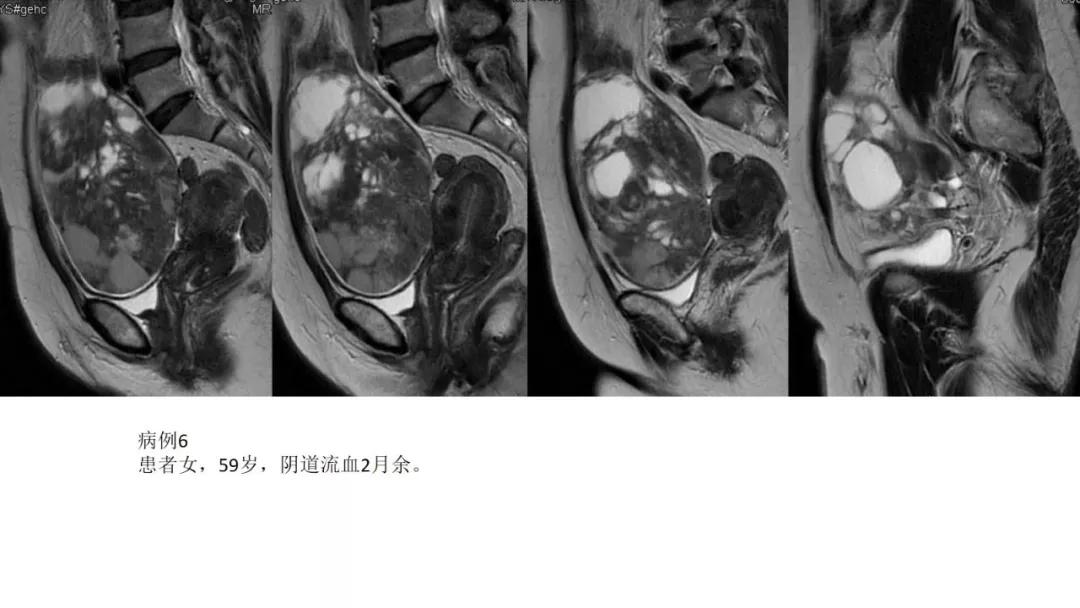

高雌激素症状:颗粒细胞瘤、卵泡膜细胞瘤(绝经期后出血及阴道不规则出血、性早熟、子宫内膜增生、乳房胀痛)